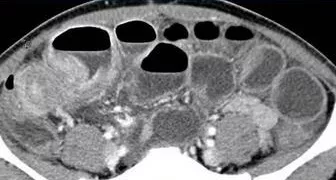

又是三周期的化疗后,曾林的直肠肿块继续缩小,保肛的希望也越来越大;然而,12月初患者因急性腹痛急诊来医院,诊断为突发肠梗阻。

肠梗阻是肠癌患者中既常见又难以避免的并发症,经过积极的内科治疗,患者肠梗阻的情况并未好转,考虑到患者的肿瘤较初治时已明显缩小,肠梗阻的情况又不容乐观,遂提前接受了手术治疗。